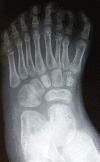

Mirror foot is a rare congenital anomaly on to the spectrum of complex foot polydactyly. It may occur in isolation or associated with other malformations or genetic syndromes. This is a subject little described in the literature, with few publications on its treatment. We herein report the case of a 4-year-old female patient who presented with a left foot with 8 fingers, without other associated deformities, whose complaints included the impossibility of wearing shoes and social stigma. Radiographically, eight metatarsi with their respective phalanges, five cuneiform bones, and absence of bone deformities in the hindfoot were verified. The surgical approach was chosen in order to promote functional and esthetic improvement, as well as a better adaptation to the use of closed shoes, according to the patient's and family's desire. A dorsal and plantar V incision was performed, with resection of three supranumerary rays, including three central metatarsi with their nine corresponding phalanges, two cuneiform bones, tendons and extra digital nerves, followed by suture of the intermetatarsal ligaments, preserving the fingers with normal appearance, decreasing the width of the foot, and maintaining proper support. The reduction was maintained through transmetatarsal fixation with Kirschner wires. The postoperative period went on with the use of a walking boot and zero load, without complications, with removal o the Kirschner wires and allowing load on the limb after twelve weeks.